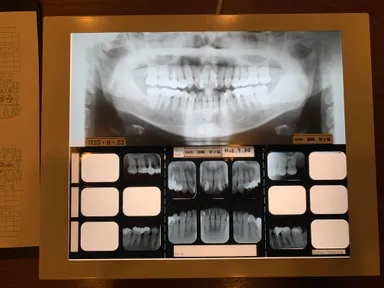

4・レントゲン・写真撮影

全体を確認できるパノラマレントゲン写真1枚と細やかな部分を確認できるデンタルレントゲン14枚。